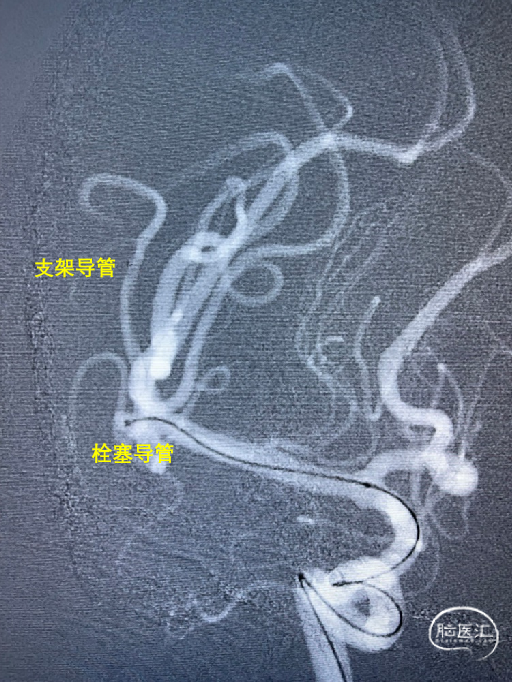

Synchro14微导丝牵引支架微导管到位;弹簧圈微导管到位。

送入3*6mm弹簧圈成篮,同时摆一根支架微导管在上干,为T型支架做准备;

释放一枚Leo baby支架 2.5*25mm。

因下干支与M1成角太锐,支架在转弯处打开,多次推拉调整,以“神龙摆尾”方式释放,将支架尾端避开上干开口。

释放支架后,再依次送入2*3mm、1.5*2mm两枚弹簧圈完成治疗。